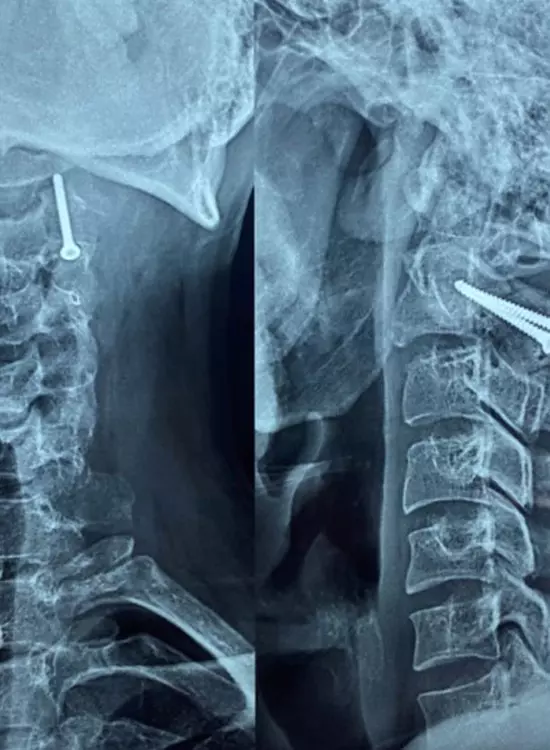

Cirugía de Columna

Galería

Galería y Medios